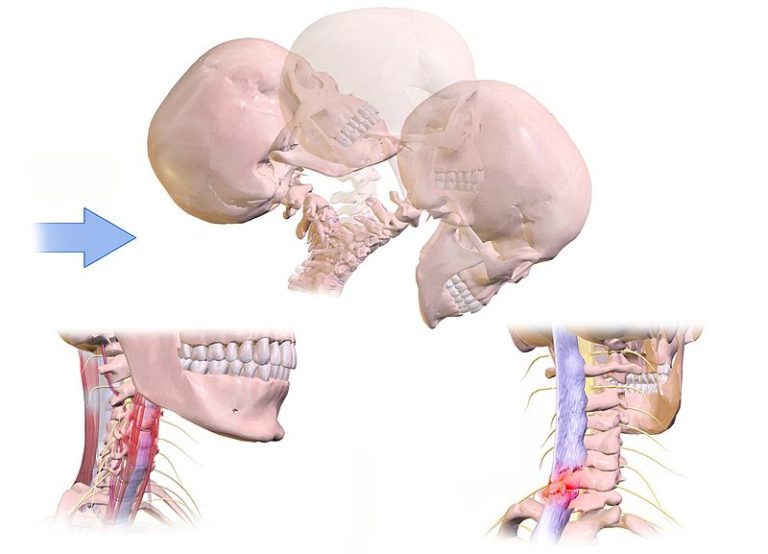

WebEs recomendable recibir el tratamiento del latigazo cervical y las pautas a seguir por un profesional fisioterapeuta. En Indemnización por Accidente, le podemos recomendar. WebLo primero que debemos hacer tras sufrir un accidente de trafico es acudir al hospital, donde nos harán las pruebas y revisiones necesarias para realizar un buen diagnóstico. WebLa causa mayormente asociada a la rectificación es el latigazo cervical, generado por fuerzas rápidas de desaceleración y aceleración que generalmente ocurren durante.